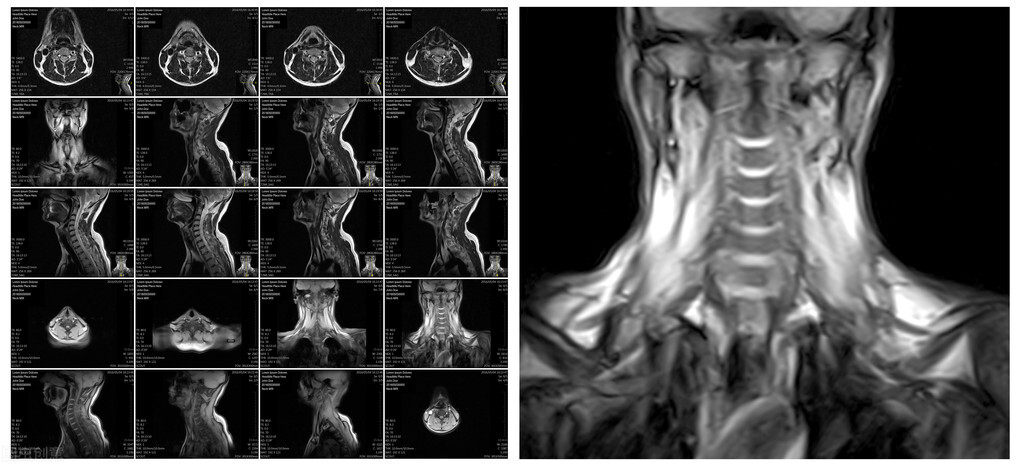

5.颈部血管,查看颈部血管的管壁、内膜、血流,判断有无斑块、血栓等。并对斑块、血栓导致的颈部血管狭窄做一个初步判断。